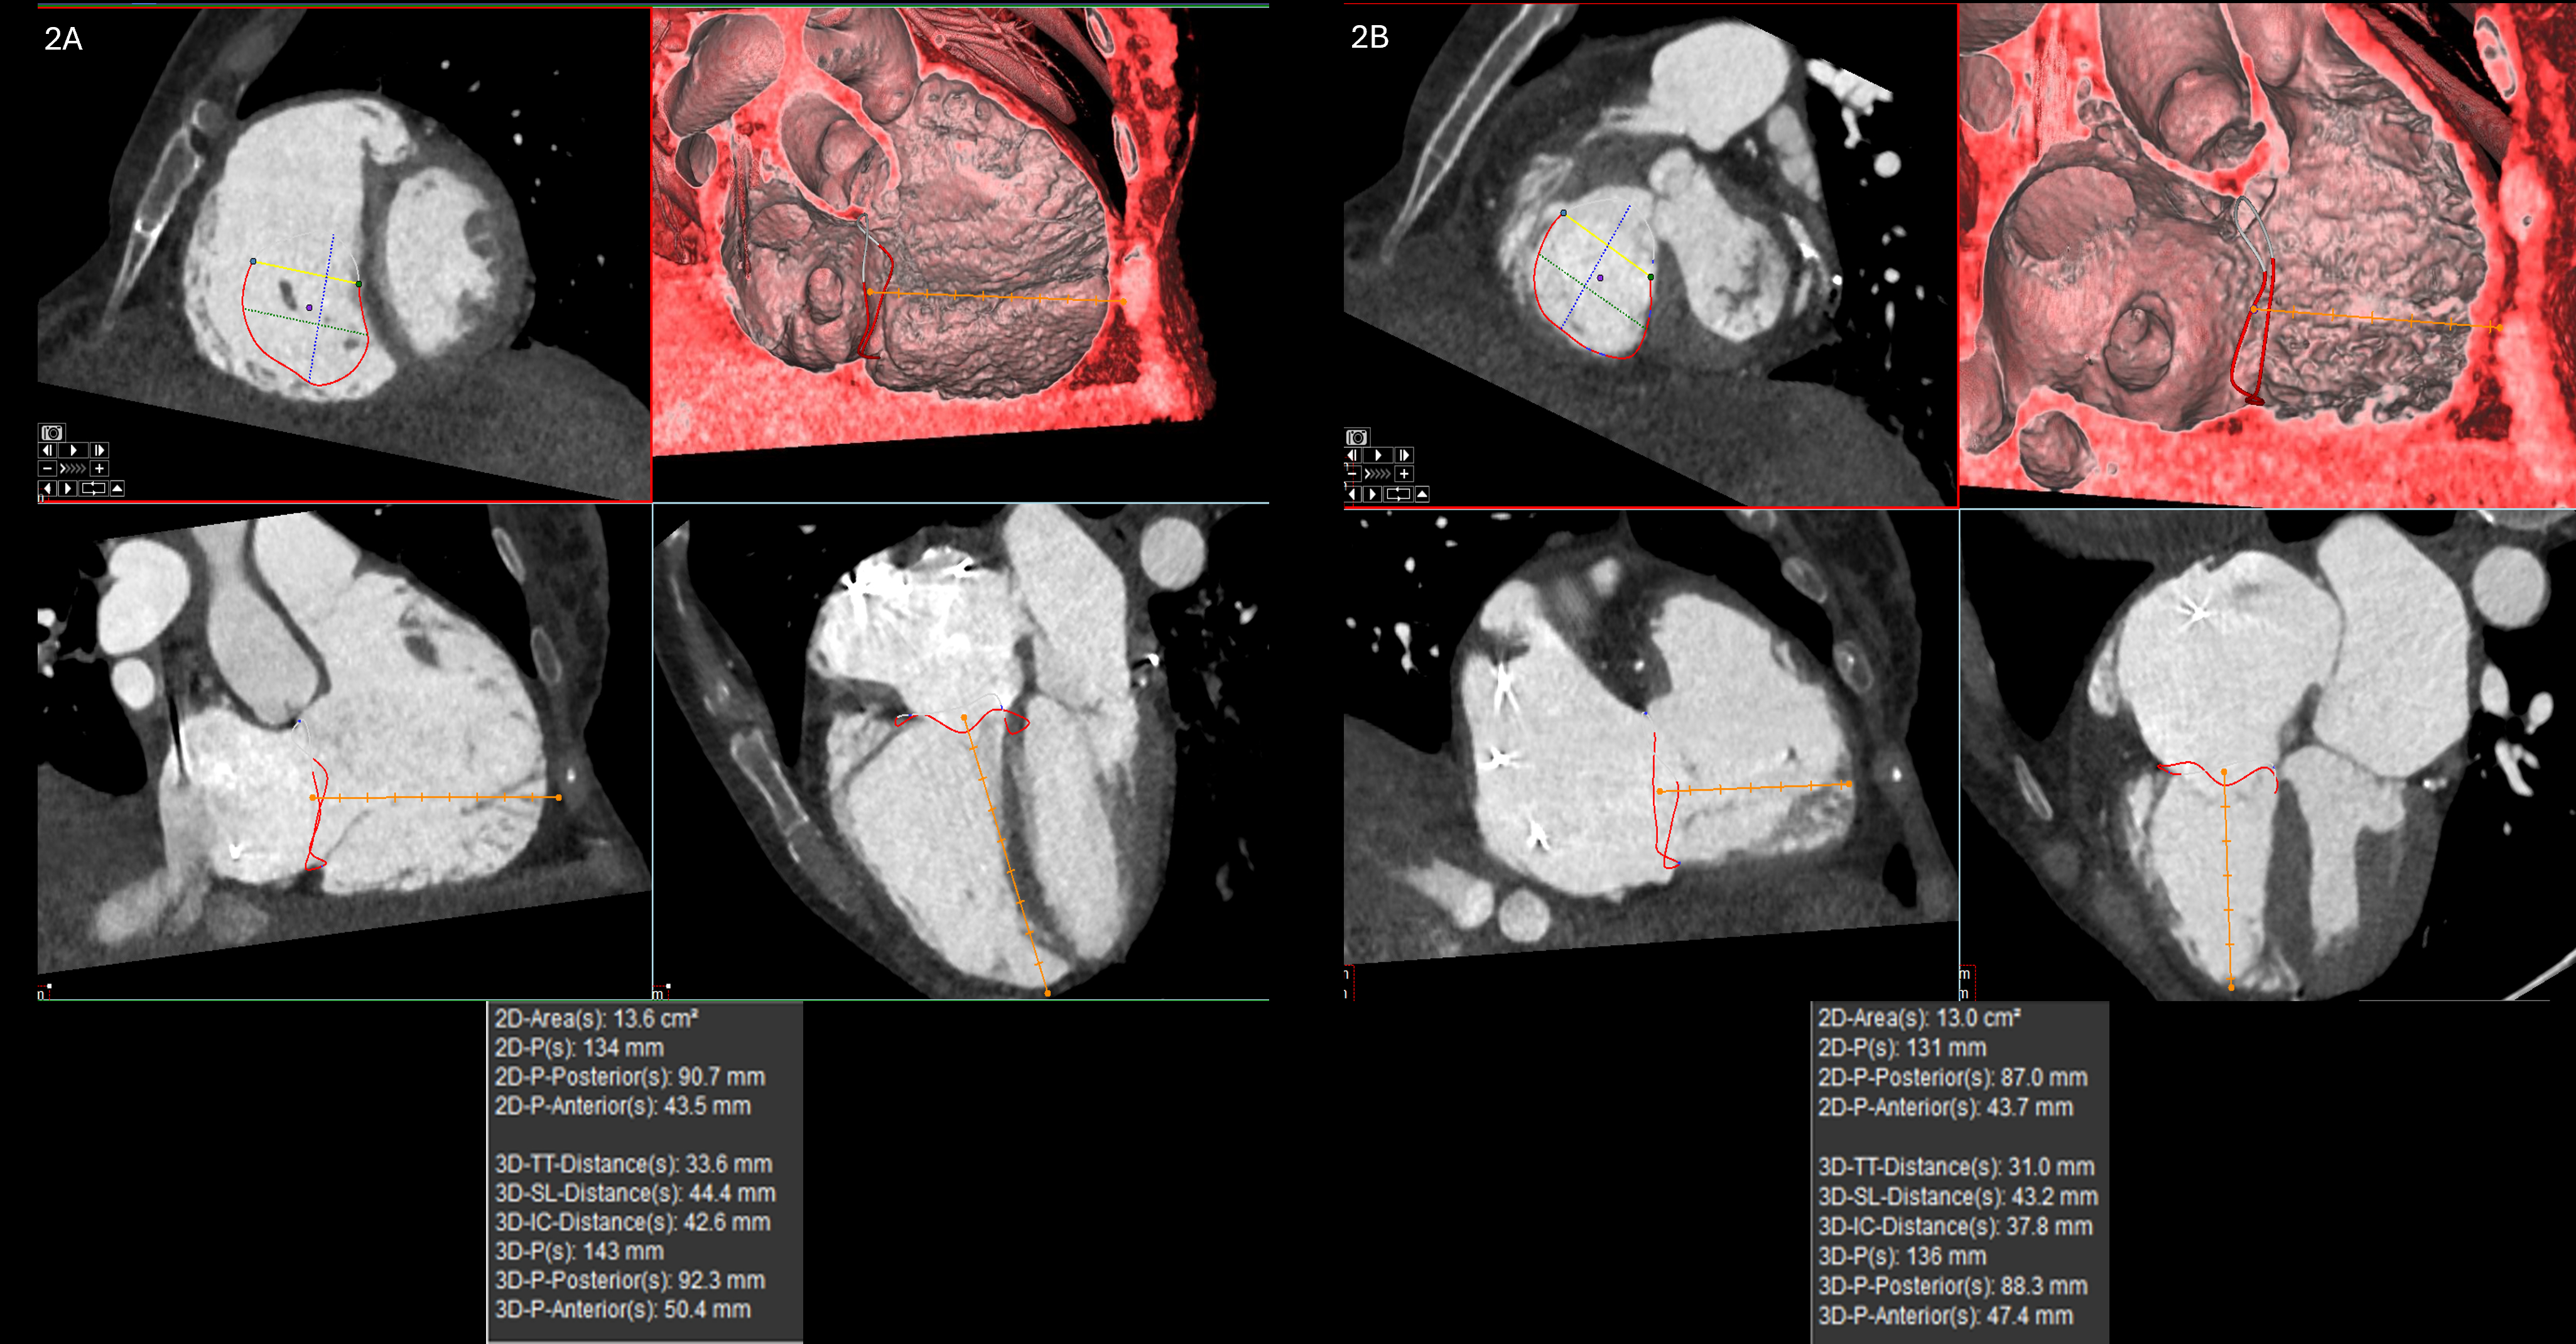

We retrospectively analyzed 19 patients with severe tricuspid regurgitation undergoing evaluation for TTVI who underwent both contrast-enhanced cardiac CT and TEE, with TEE performed a median of 93 days after CT (range: 0–247 days). Tricuspid annular dimensions were generated using an AI-powered 3D semiautomated analysis (3D Auto TV; Philips Ultrasound). CT annular measurements were independently performed in duplicate using the Aquarius iNtuition software. AI-generated echo measurements were visually reviewed and confirmed to ensure accuracy. Annular dimensions were measured in both diastole and systole using 2D and 3D perimeter-based diameter dimensions (perimeter/π) for both TEE and CT-derived measurements. Agreement between TEE and CT-derived dimensions was assessed with Pearson correlation coefficient. Inter-observer variability was assessed for CT-derived measurements of10 patients.

There was strong correlation between diastolic 2D TEE and CT dimensions (r = 0.564, p = 0.036). Intraclass correlation coefficient (ICC) analysis showed excellent reliability for 2D diastolic (ICC = 0.925) and 3D diastolic (ICC = 0.935) measurements. Systolic measurements showed slightly lower but strong agreement (2D ICC = 0.824; 3D ICC = 0.810). All ICC values were significant (p < 0.001). Interobserver variability for the CT scan measurements showed excellent agreement across all 2D and 3D tricuspid annulus measurements (ICC range: 0.916–0.969; all p < 0.001).